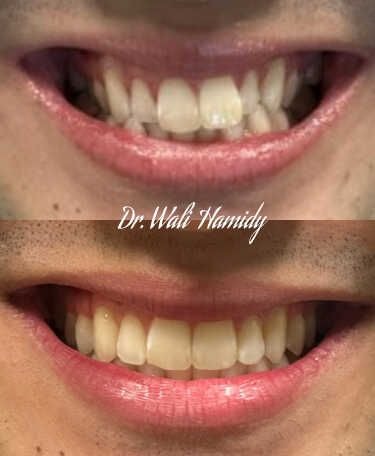

Check out our Invisalign® treatment gallery to see how this orthodontic service can straighten your teeth and improve your smile. Contact La Jolla Dental Image at 858-202-0481 today to make an appointment with our dentist, Dr. Wali Hamidy, and learn more about Invisalign clear aligners in La Jolla, California.